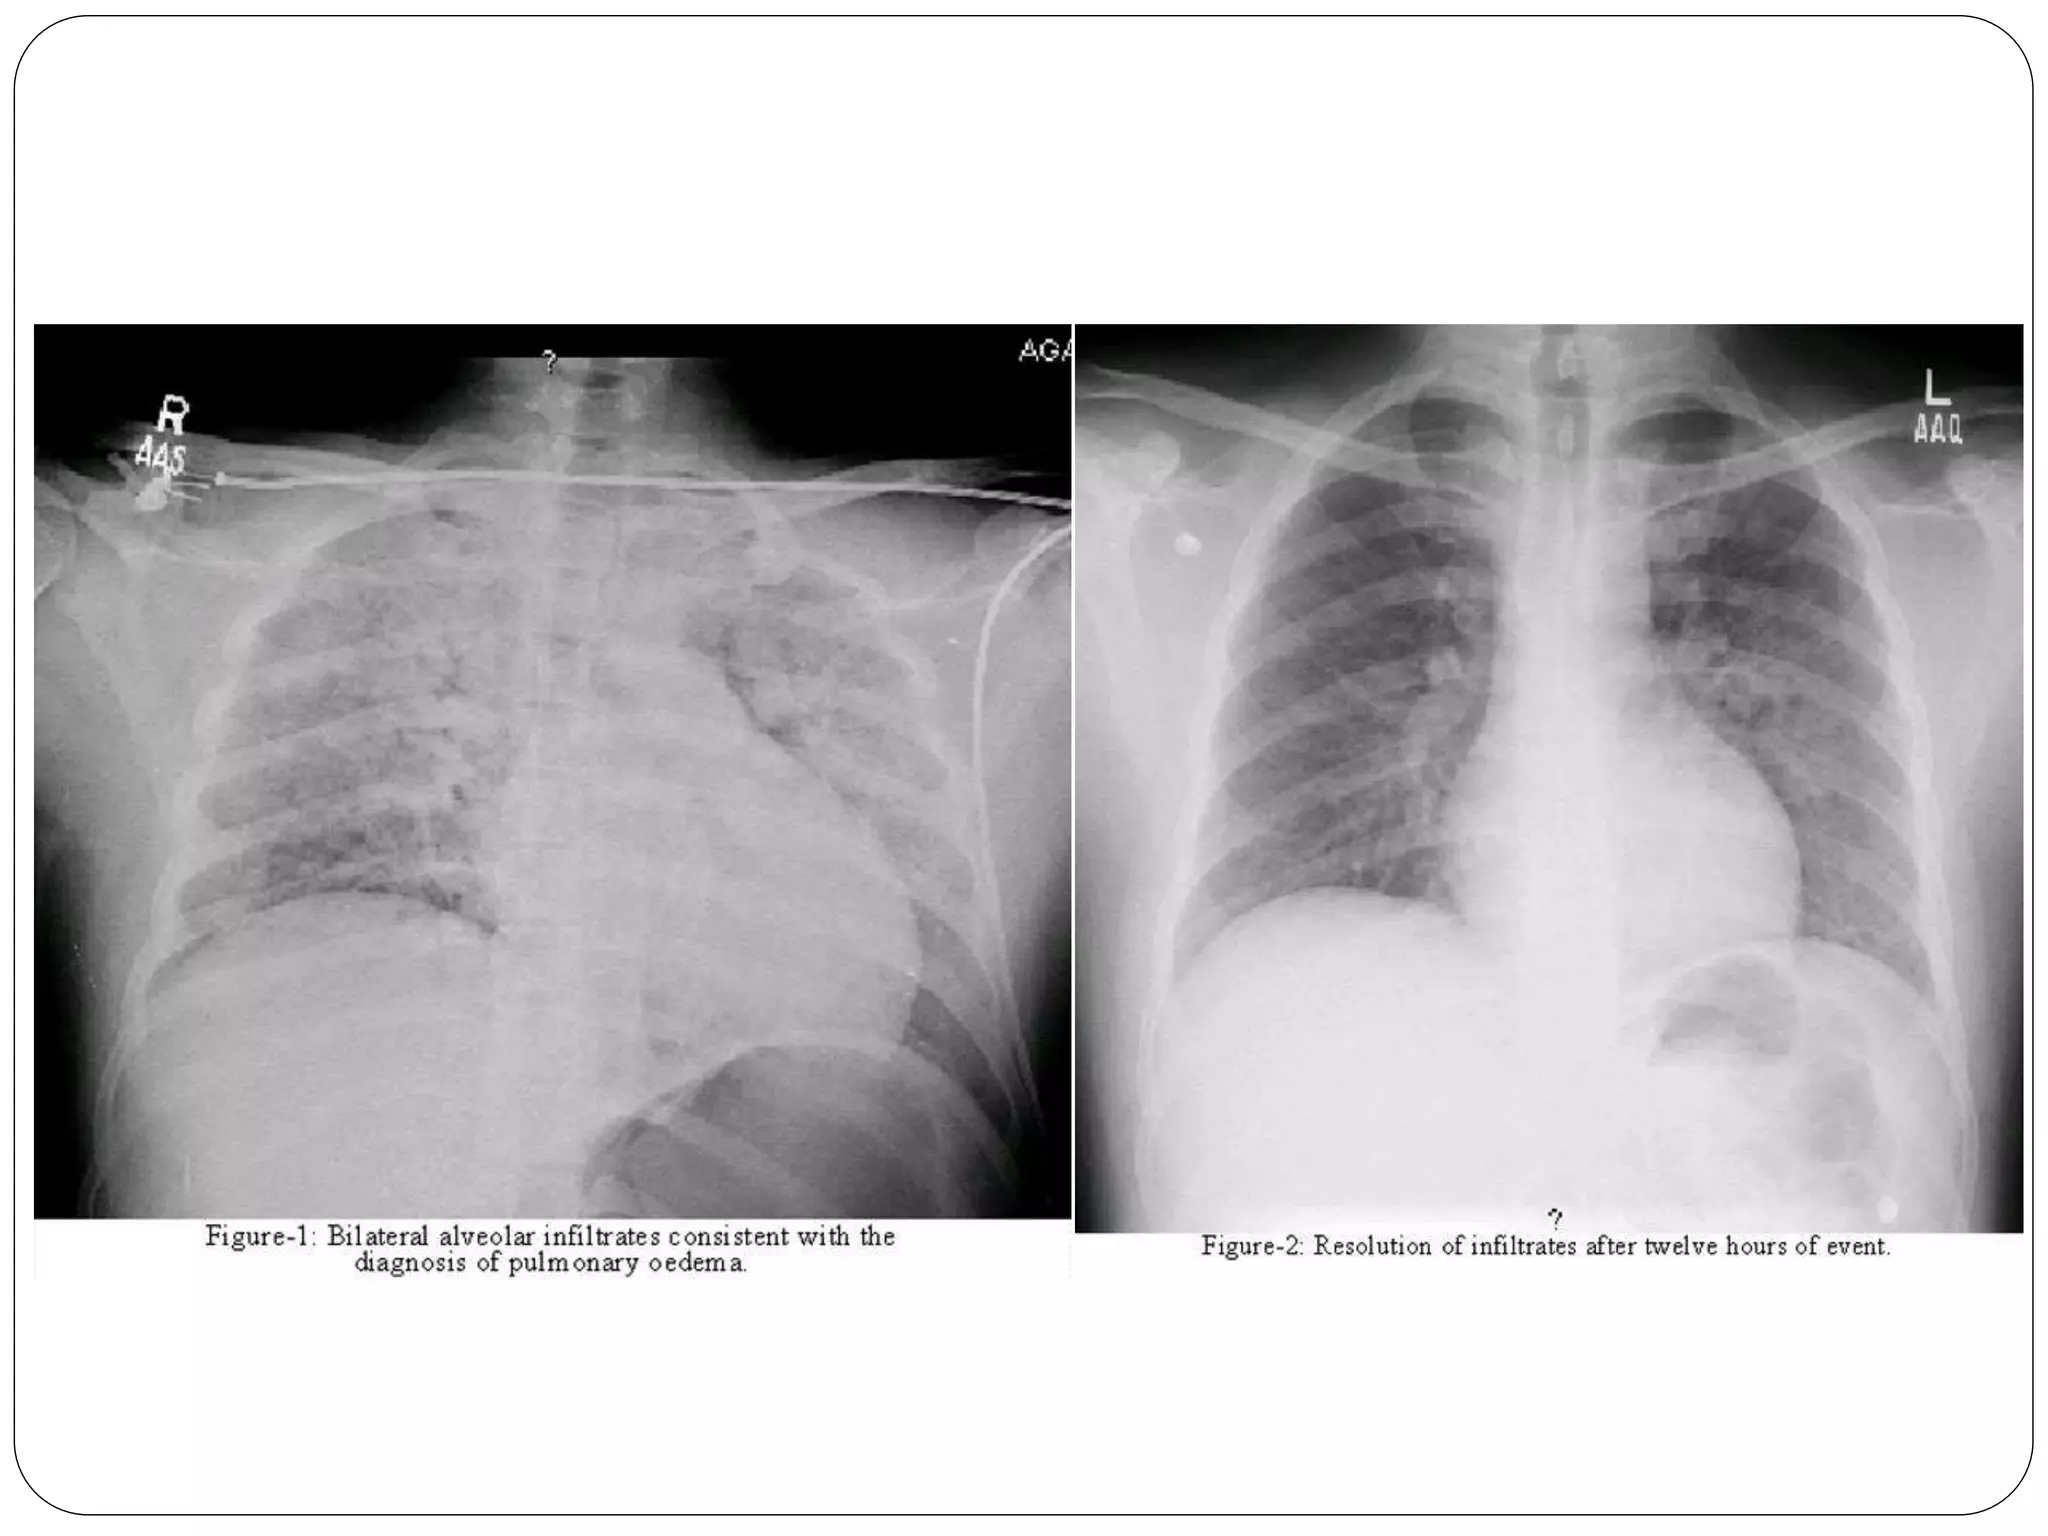

 Both clinical and radiological features usually resolve

within 24 h with no sequelae, although delayed

presentation of up to 24 h, and progression to acute

lung injury and death have also been reported.